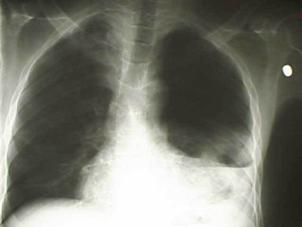

Pneumotorace sufocant bilateral Pneumotorace sufocant stang

Pneumotorace

sufocant stang Pneumotorace